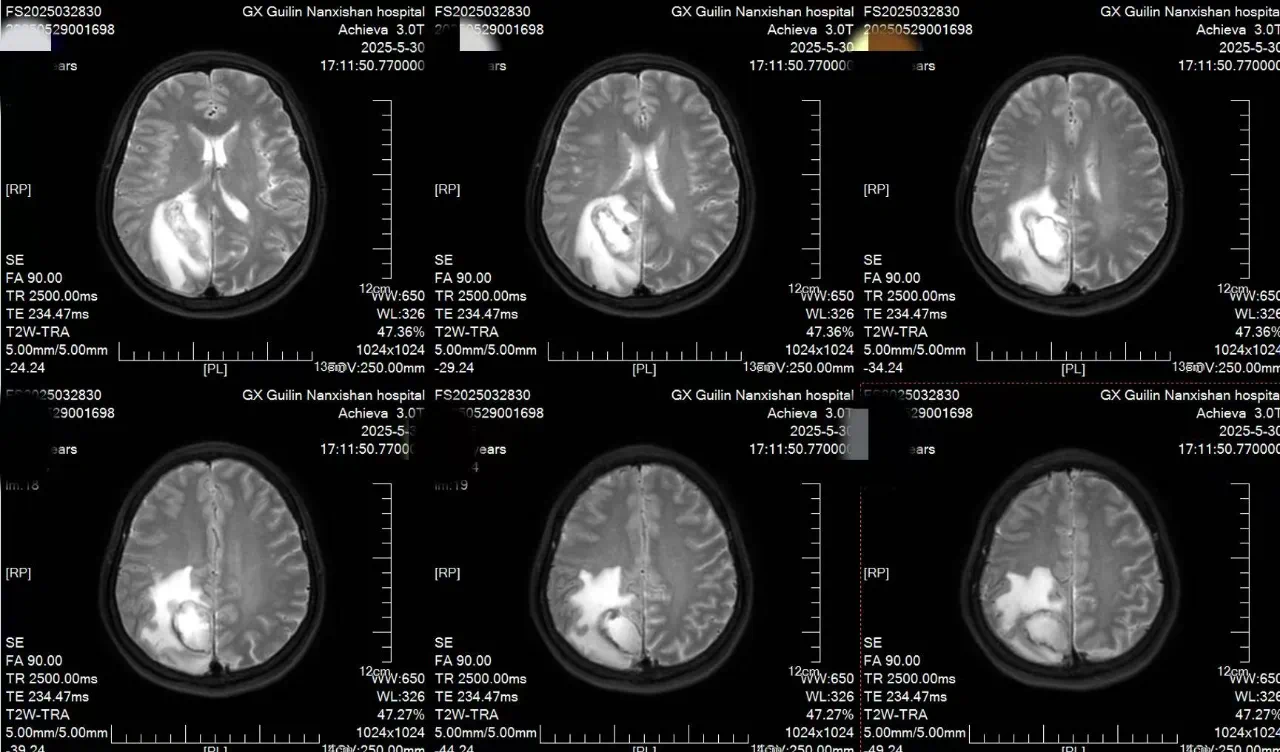

患者李女士自诉约2天前无明显诱因出现头痛,疼痛性质为阵发性胀痛,可自行缓解,伴有左侧肢体乏力,行走不稳。在本地医院检查后诊断:右侧顶叶占位性病变并周围脑组织水肿。为进一步治疗,来到南溪山医院就诊,完善各项检查后确诊为:功能区脑脓肿。

面对李女士的病情,神经外科团队经过反复讨论,决定采用机器人辅助实时可视化抽吸微创手术。手术前,团队通过3D影像重建技术,为李女士的脑部构建了精准的三维模型,清晰标注出脓肿的大小、形态以及与周围血管、神经的位置关系。手术机器人则根据这些数据,自动规划出最优穿刺路径,误差可控制在0.5毫米以内。

在机器人“导航”系统的引导下,神经外科主任王文波主任医师手持穿刺针,沿着预设路径稳步推进。术中,实时影像系统如同“透视眼”,清晰显示穿刺针的位置和脓肿内部情况,医生可以动态观察抽吸过程,确保每一步操作都精准无误。传统开颅手术需要打开十几厘米的切口,创伤大、恢复慢,还可能引发感染。而机器人辅助手术不仅创伤小,还能最大限度减少对正常脑组织的干扰。术后李女士肢体功能逐渐恢复,一周后完全恢复。